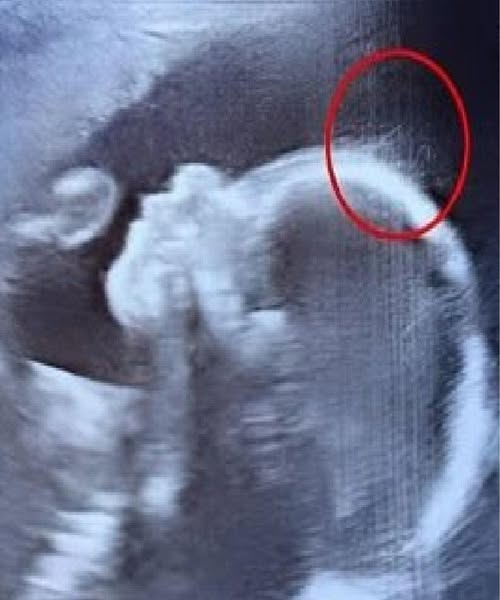

“Wait a minute,” she said with a mix of confusion and delight. “Is that… hair?”

A nearby doctor stepped forward, squinting at the screen, then laughed.

“Looks like you’ve got a little rock star in there,” he joked. “She might just skip baby baldness altogether!”